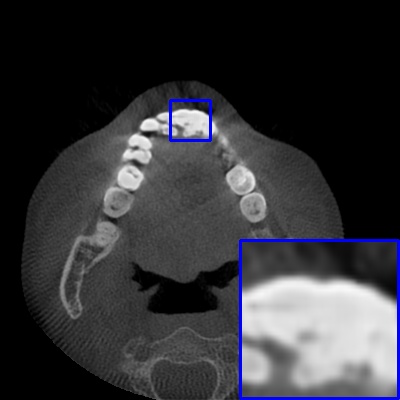

Figure 4: Comparison of MAR images by different methods on real-world MA image. The last image is the metal mask by selecting the pixel area over 2800HU in the MA image.

Results on real-world MAR. We also compare these methods on dental CBCT images with real-world metal artifacts. The visual results on one sample are shown in Fig. 4. We observe that our MARformer-T and MARformer-L well seperate the adjacent teeth and retain their shapes. This shows that our MARformers, though trained on synthetic data, are effective on real-world MAR.